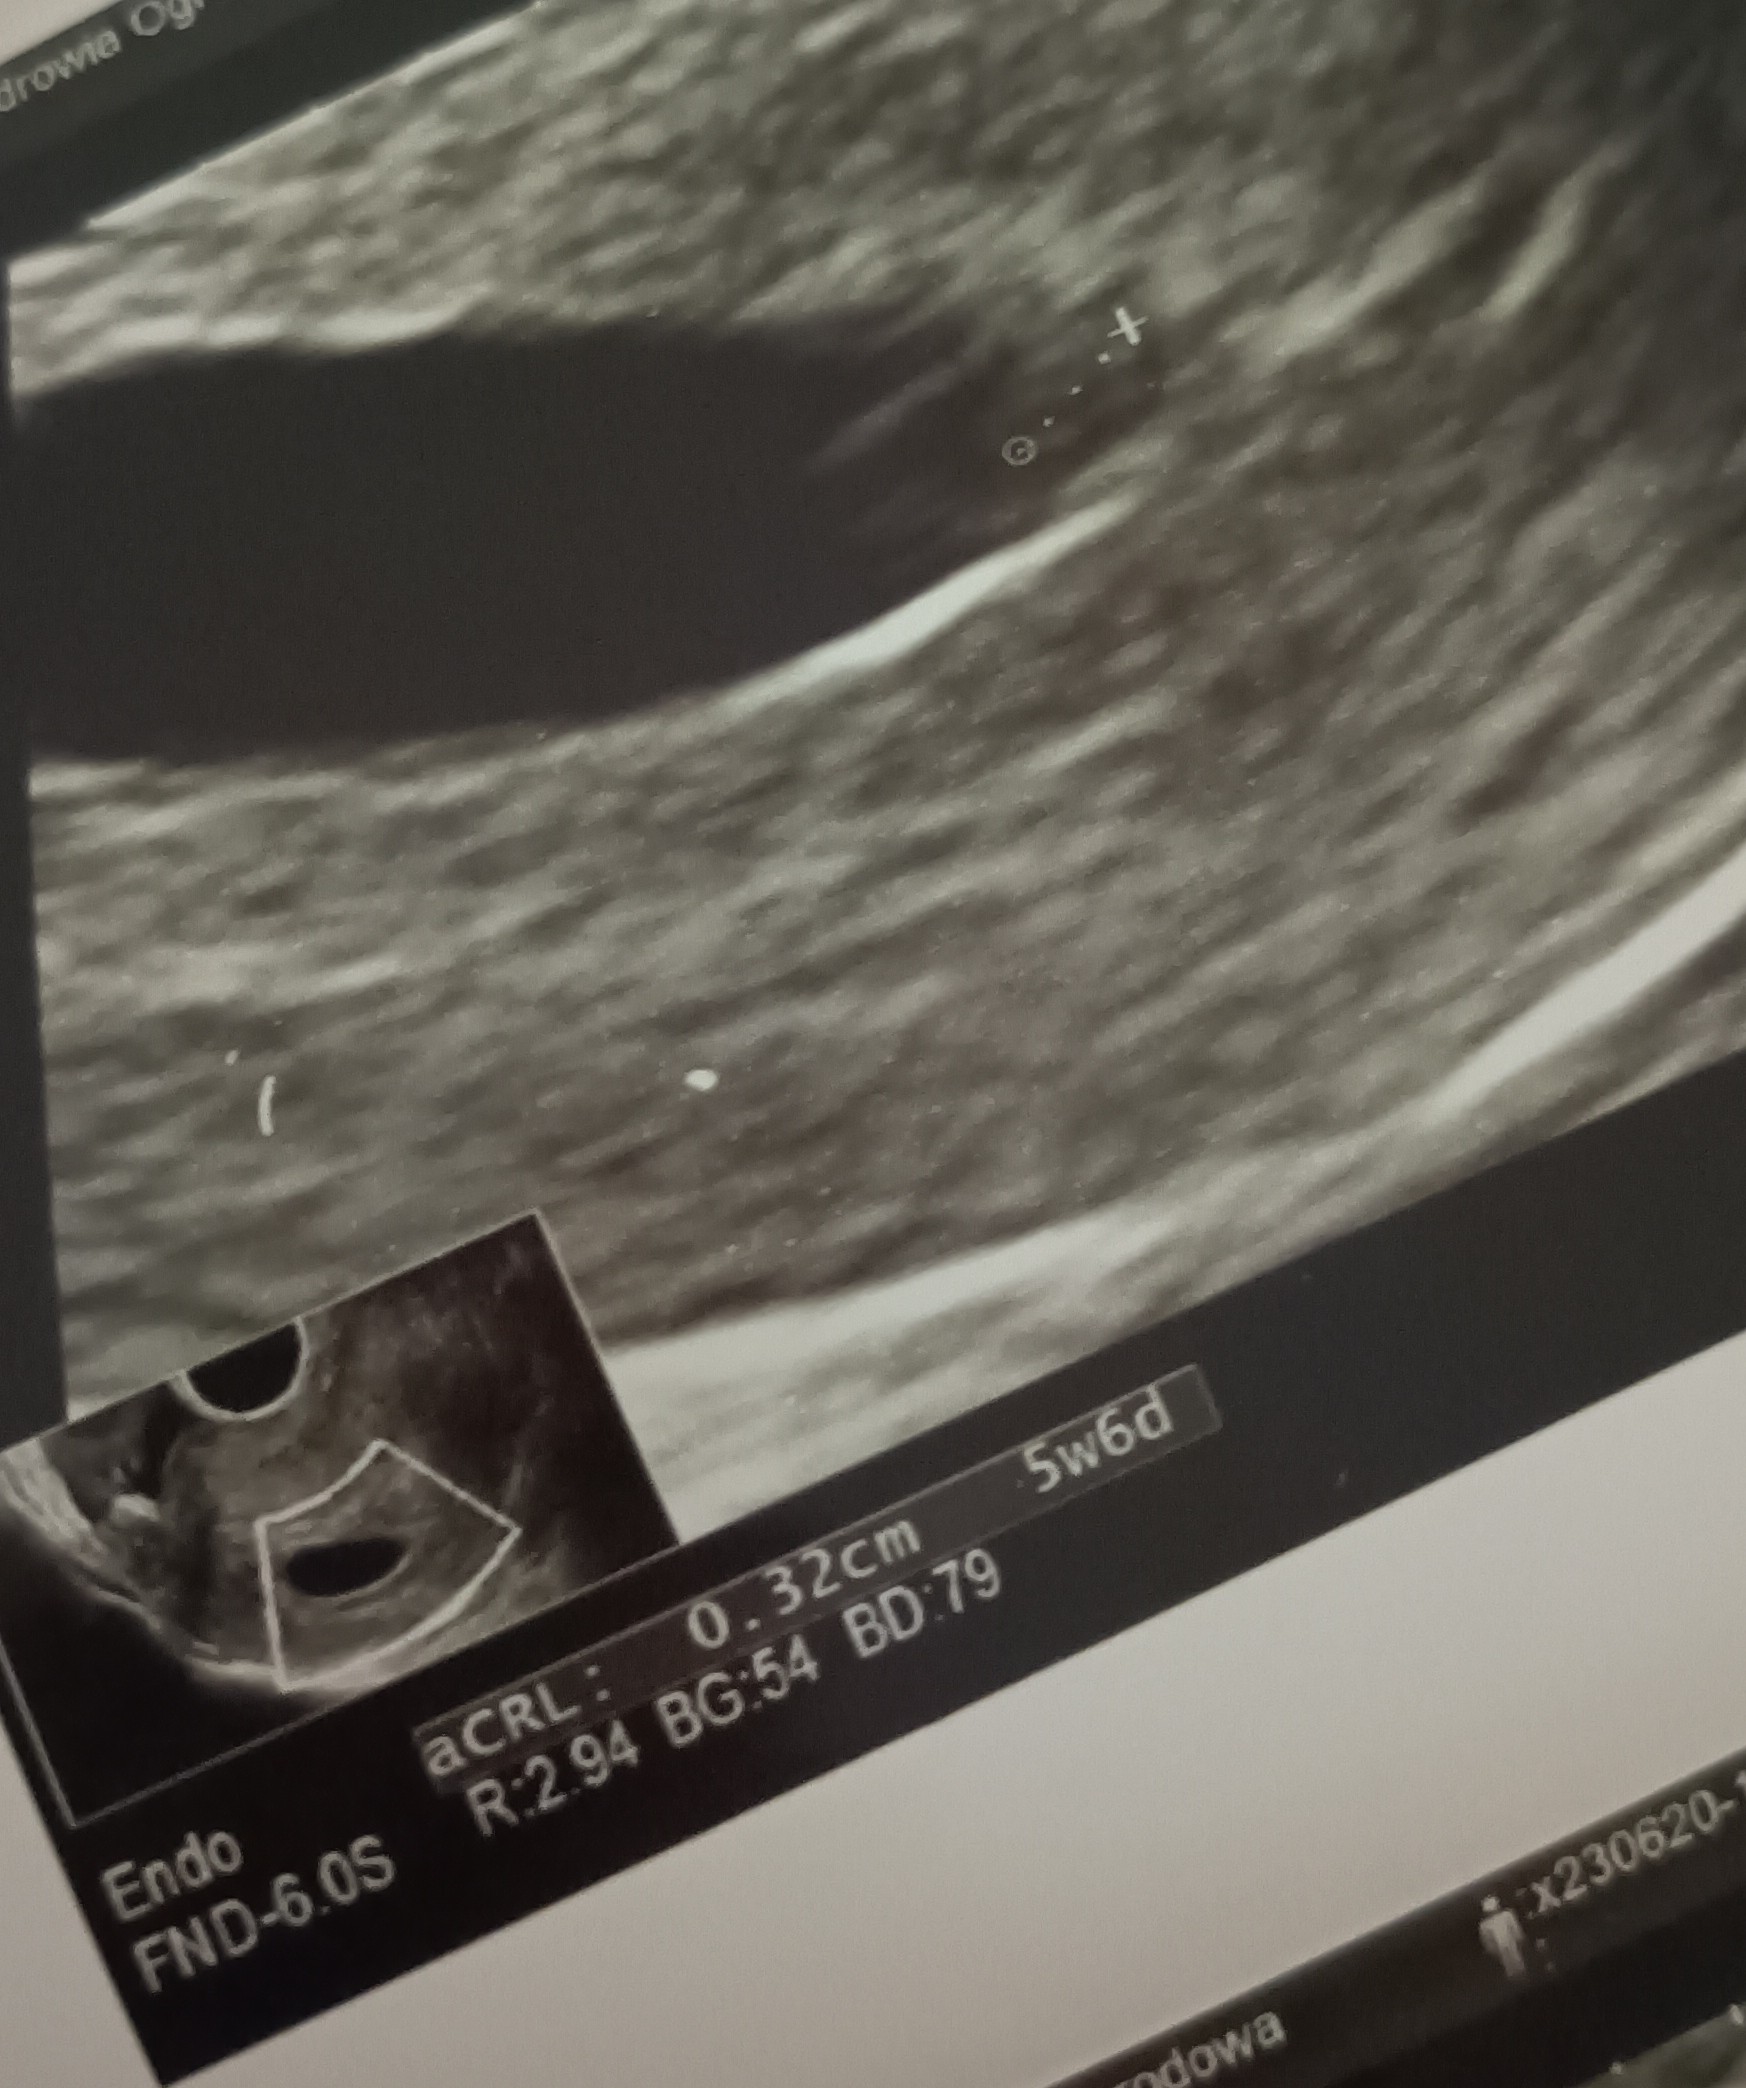

Chciałabym się nieśmiało przywitać. Jestem (a przynajmniej mam taką nadzieję) w pierwszej ciąży, wg aplikacji termin porodu to 16.02. Szukałam kilku informacji na temat ciąży i trafiłam na to forum. Nie ukrywam, że o ciąży wie tylko mój mąż i brakuje mi trochę kobiecych rad. Jestem w tym temacie dość zielona. Nie chcę na razie nikomu mówić, bo nie jestem jakąś specjalną optymistką. Wynik testów ciążowych lekko mnie zdziwił, ponieważ miałam (moim zdaniem) wszystkie objawy zapowiadające @. Dla potwierdzenia miałam robione badanie beta HCG. Do wczoraj jedynym objawem jaki miałam było pobolewanie podbrzusza tak jak na okres, przepisano mi duphaston 3x1. Najbardziej martwi mnie fakt, że w tym momencie nie mam żadnych objawów ciąży, ani razu mnie nie mdliło, nie zmieniają mi się smaki, mam lekko bolące piersi, ale zastanawiam się czy to nie sprawka duphastonu. Pojutrze idę do ginekologa i mam taką ogromną nadzieję, że wszystko będzie dobrze, a równocześnie boję się, że nic z tego nie będzie